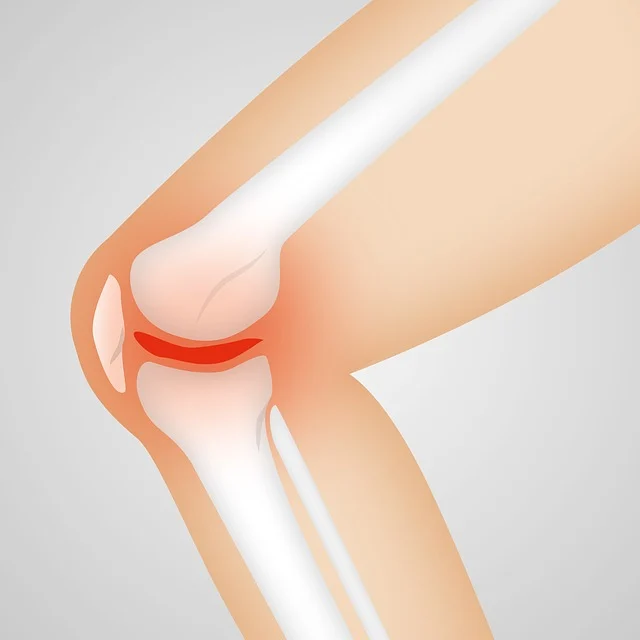

콘드로이친은 연골을 보호하고 관절 기능을 향상시키는 중요한 성분입니다. 특히 퇴행성 관절염이 걱정되는 분들, 운동 후 피로가 쌓인 관절을 관리하고 싶은 분들에게 매우 유익한 보조제가 될 수 있습니다. 꾸준한 복용과 함께 적절한 운동을 병행한다면, 관절 건강을 효과적으로 지킬 수 있습니다. 🦵

👩⚕️ 관절에 부담을 덜어주고 유연함을 유지하려면, 오늘부터 콘드로이친을 복용해보세요! 건강한 관절로 더 활기찬 일상을 보내실 수 있을 거예요.